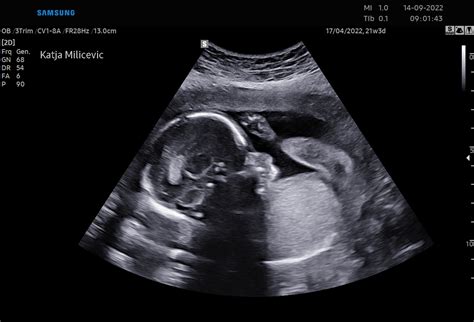

Med 11. in 14. tednom nosečnosti je običajno opravljen test prvega trimesečja, ki vključuje merjenje nuhalne svetline in krvne preiskave. Cilj tega testa je oceniti verjetnost za kromosomske nepravilnosti. Pri nosečnicah, ki pričakujejo dvojčke, se ultrazvočno že lahko ugotovi, ali gre za enojajčna ali dvojajčna dvojčka, ter ali delita eno ali dve posteljici.

Če še niste opravili prvega ultrazvočnega pregleda, je zdaj čas, da se dogovorite za termin. Ta pregled je ključen za spremljanje razvoja vašega dojenčka in potrditev nosečnosti. Razmislite tudi o vpisu v šolo za starše, ki vam lahko nudi dragoceno znanje o porodu, negi dojenčka in dojenju. Programi, kot je Šola za starše na Nosecka.net, ki so ustvarjeni v sodelovanju z zdravniki, ponujajo celovito pripravo na prihod novega družinskega člana.